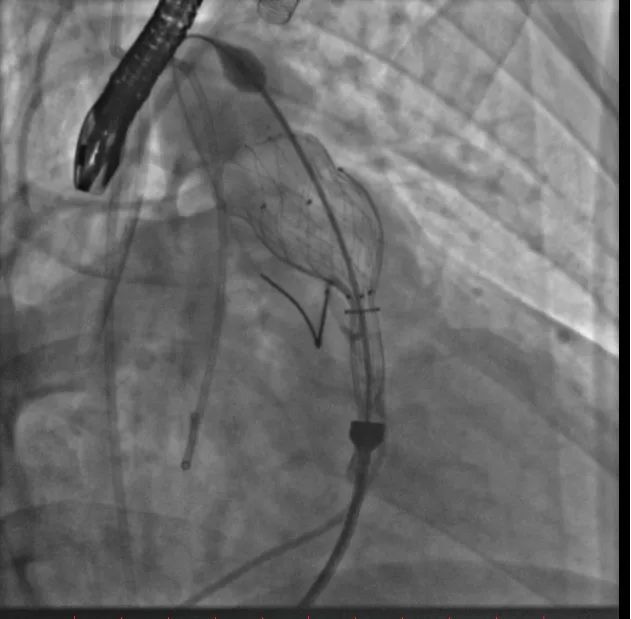

术中测量患者基础主动脉、肺动脉、右心室压力分别为111/58mmHg、31/4/13mmHg、34/1/6mmHg,通过肺动脉造影,术中测量球囊内径为32mm(见图二),选择36-25mm VENUS-P肺动脉瓣膜,在肺动脉造影指引下逐步打开瓣膜。考虑到患者肺动脉分叉较短,存在瓣膜释放后移位风险,故选择高位释放法(图三)。但释放瓣膜后造影提示右肺动脉开口局部被阻挡(图四),复测患者主肺动脉、左肺动脉、右肺动脉压力分别为57/13/25mmHg、55/12/24mmHg、27/7/14mmHg。

图四:主肺动脉造影及选择性右肺动脉造影提示右肺动脉开口局部被阻挡